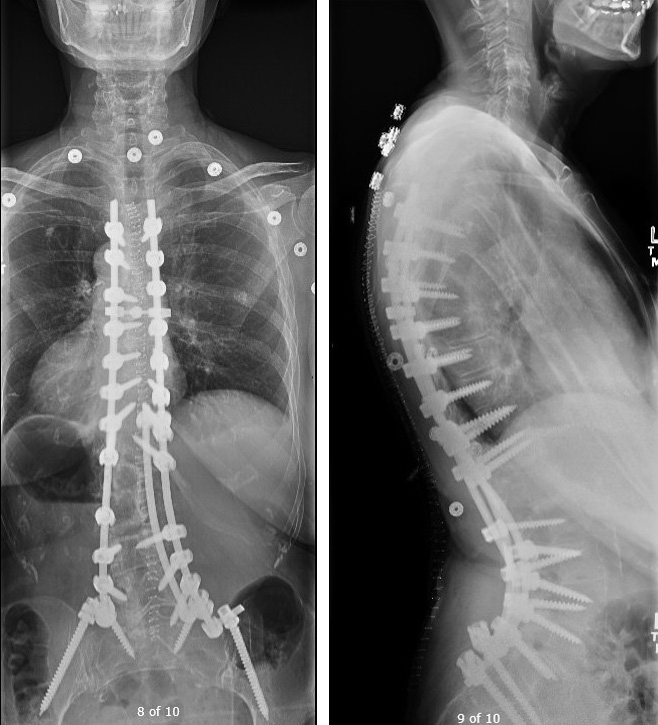

척추가 이렇게 휘게 되면 일상생활에 지장이 없는 경우는 많습니다. 하지만 만곡이 심해지는 경우 심폐합병증이 가장 치명적이고 무서운 합병증이 될 수 있습니다. 일단 기본적으로 whole spine X-ray 를 촬영하여 척추의 pedicle 의 회전과 만곡의 정도를 cubbs angle 등으로 측정을 하게 됩니다.

척추 측만증에서 수술을 하게 되면 fusion 을 주로 하게 됩니다.

주만곡을 꼭 모두 유합을 해야하며, 유연성이 있는 보상성 만곡은 유합할 필요가 없습니다.

만곡 상부의 neutral vertebra 부터 하부의 neutral vertebra 까지 유합을 합니다. 따라서 척추체의 회전의 유무가 중요하게 됩니다.

유합의 가장 하단은 stable vertebra 로 sacral central line이 가운데를 지나가도록 해야합니다.

흉추의 후만 및 요추의 전만각은 정상에 가깝게 교정해야합니다.